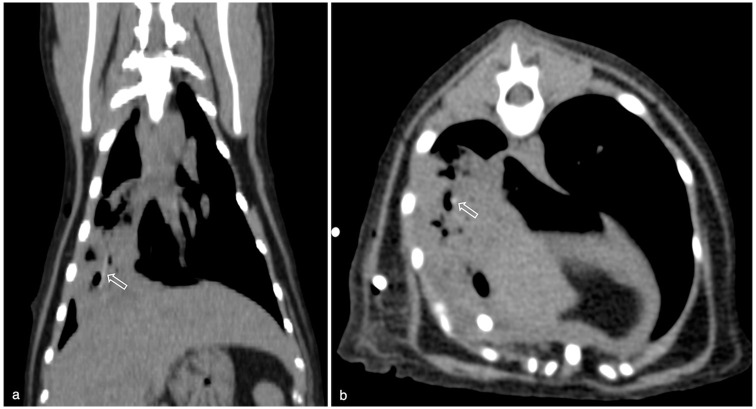

ObjectivesThe purpose of this retrospective, descriptive study was to assess CT findings and short-term outcome of cats with pyothorax presented to a referral hospital.MethodsThoracic CT studies of 41 cats with pyothorax comprising pre-contrast lung and soft tissue reconstructions and post-contrast soft tissue reconstructions were blindly reviewed by two European College of Veterinary Diagnostic Imaging (ECVDI) board-certified radiologists and a third-year ECVDI resident, referencing a predetermined list of imaging features. Clinical outcomes, including treatment options, survival to discharge and length of hospitalisation, were recorded.ResultsAll cats (100%) had pleural effusion. Common imaging findings included intrathoracic lymphadenomegaly (85%), pleural thickening (85%), presence of pannus (81%) and evidence of pneumonia (49%). Pulmonary abscessation was suspected in 22% of cats and foreign bodies in 12%. Of the 41 cats, 20 were managed medically, 20 underwent surgery and one had unsuccessful medical treatment followed by surgical intervention. The median duration of hospitalisation was 7 days, and 36 cats survived to discharge.Conclusions and relevanceThis study demonstrates that cats with pyothorax commonly have marked changes on CT that involve multiple thoracic compartments. Our study population highlights that feline pyothorax can have a good short-term outcome when managed either medically or surgically.

Abstract Image